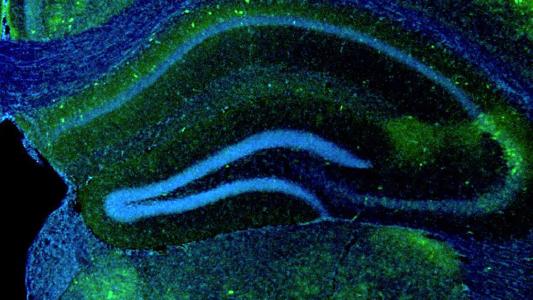

How a mutation in microglia elevates Alzheimer’s risk

A study finds that microglia with mutant TREM2 protein reduce brain circuit connections, promote inflammation, and contribute to Alzheimer’s.